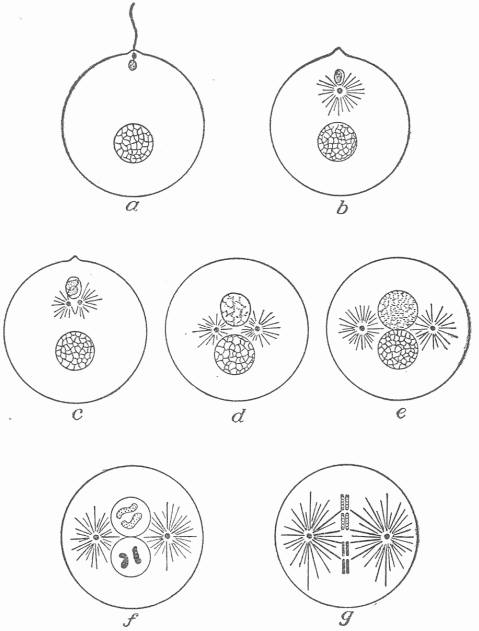

- Classification Of The Organisms Which Cause Disease.—Bacteria: Size, Shape, Structure, Capacity For Growth, Multiplication And Spore Formation.—The Artificial Cultivation Of Bacteria.—The Importance Of Bacteria In Nature.—Variations In Bacteria.—Saprophytic And Parasitic Forms.—Protozoa.—Structure More Complicated Than That Of Bacteria.—Distribution In Nature.—Growth And Multiplication.— Conjugation And Sexual Reproduction.—Spore Formation.—The Necessity For A Fluid Environment.—The Food Of Protozoa.—Parasitism.—The Ultra-Microscopic Or Filterable—Organisms.—The Limitation Of The Microscope.—Porcelain Filters To Separate Organisms From A Fluid.— Foot And Mouth Disease Produced By An Ultra-Microscopic Organism.— Other Diseases So Produced.—Do New Diseases Appear?

A simple conception of health and disease can be arrived at by the study of these conditions in a unicellular animal directly under a microscope, the animal being placed on a glass slide. For this purpose a small organism called "Amoeba" (Fig. 2), which is commonly present in freshwater ponds, may be used. This appears as a small mass, seemingly of gelatinous consistency with a clear outline, the exterior part homogeneous, the interior granular. The nucleus, which is seen with difficulty, appears as a small vesicle in the interior. Many amoebæ show also in the interior a small clear space, the contractile vesicle which alternately contracts and expands, through which action the movement of the intracellular fluid is facilitated and waste products removed. The interior granules often change their position, showing that there is motion within the mass. The amoeba slowly moves along the surface of the glass by the extension of blunt processes formed from the clear outer portion which adhere to the surface and into which the interior granular mass flows. This movement does not take place by chance, but in definite directions, and may be influenced. The amoeba will move towards certain substances which may be placed in the fluid around it and away from others. In the water in which the amoebæ live there are usually other organisms, particularly bacteria, on which they feed. When such a bacterium comes in contact with an amoeba, it is taken into its body by becoming enclosed in processes which the amoeba sends out. The enclosed organism then lies in a small clear space in the amoeba, surrounded by fluid which has been shown to differ in its chemical reaction from the general fluid of the interior. This clear space, which may form at any point in the body, corresponds to a stomach in a higher animal and the fluid within it to the digestive fluid or gastric juice. After a time the enclosed organism disappears, it has undergone solution and is assimilated; that is, the substances of which its body was composed have been broken up, the molecules rearranged, and a part has been converted into the substance of the amoeba. If minute insoluble substances, such as particles of carmine, are placed in the water, these may also be taken up by the amoeba; but they undergo no change, and after a time they are cast out. Under the microscope only the gross vital phenomena, motion of the mass, motion within the mass, the reception and disintegration of food particles, and the discharge of inert substances can be observed. The varied and active chemical changes which are taking place cannot be observed.

Up to the present it has been assumed that the environment of the amoeba is that to which it has become adapted and which is favorable to its existence. Under these conditions its structure conforms to the type of the species, as do also the phenomena which it exhibits, and it can assimilate food, grow and multiply. If, during the observation, a small crystal of salt be placed in the fluid, changes almost instantly take place. Motion ceases, the amoebæ appear to shrink into smaller compass, and they become more granular and opaque. If they remain a sufficiently long time in this fluid, they do not regain their usual condition when placed again in fresh water. None of the phenomena which characterized the living amoebæ appear: we say they are dead. After a time they begin to disintegrate, and the bacteria contained in the water and on which the amoebæ fed now invade their tissue and assist in the disintegration. By varying the duration of the exposure to the salt water or the amount of salt added, a point can be reached where some, but not all, of the amoebæ are destroyed. Whether few or many survive depends upon the degree of injury produced. Much the same phenomena can be produced by gradually heating the water in which the amoebæ are contained. It is even possible gradually to accustom such small organisms to an environment which would destroy them if suddenly subjected to it, but in the process of adaptation many individuals will have perished.